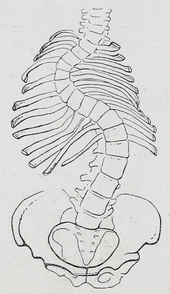

| A drawing of scoliosis | |

Scoliosis is a medical condition in which a person's spine has a sideways curve.[2] The curve is usually "S" or "C" shaped.[2] In some the degree of curve is stable, while in others it increases over time. Mild scoliosis does not typically cause problems, while severe cases can interfere with breathing.[3][4] Pain is typically not present.[5]

Scoliosis is defined as a three-dimensional deviation in the axis of a person's spine[8] In the diagnostic sense it is defined as a spinal curvature of more than 10 degrees to the right or left as the examiner faces the person, i.e. in the coronal plane. Deformity may also exist to the front or back as the examiner looks at the person from the side, i.e. in the sagittal plane.